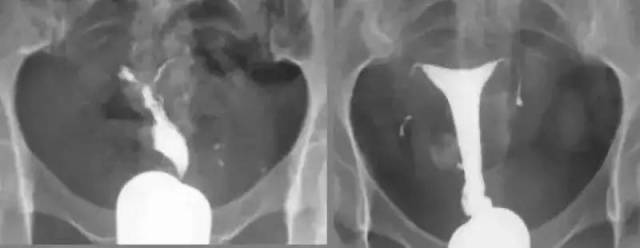

子宫输卵管造影检查的临床应用

图片尺寸960x720